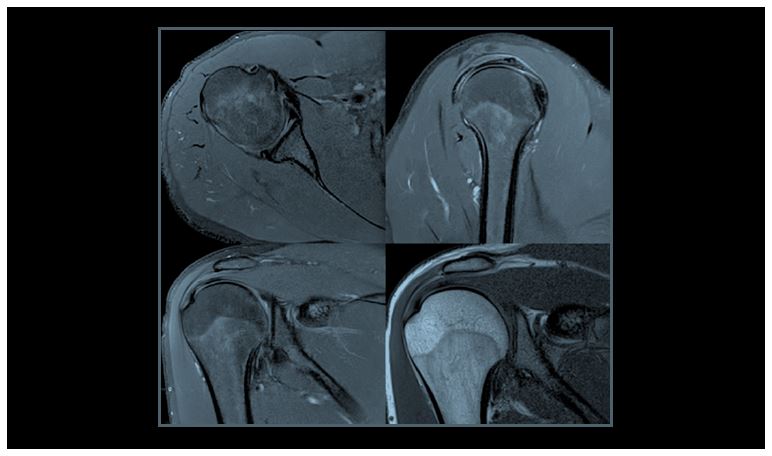

Клінічні зображення МСК з використанням 16-канальної гнучкої котушки

Рис. 14. Зображення плеча